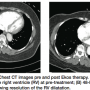

SEATTLE II began in June 2012 with the goal of 150 patients. Enrollment is going extremely well and over halfway at this point. The trial has two endpoints. First, efficacy: measuring the improvement in right ventricular/left ventricular ratio after use of the ultrasound-assisted thrombolysis catheter in submassive or massive pulmonary embolism (PE). Patients get a pre-treatment computed tomography angiography (CTA) of the chest, we perform the treatment, and then the patient undergoes a post treatment CTA of the chest 48 hours later. The second endpoint is safety: looking at the complications that may develop during treatment.

We also measure pulmonary artery pressures pre and post treatment. After we treat the patient, the PA pressure can be measured through the existing Ekos catheter with the patient in the ICU. We have seen a nice reduction in pulmonary hypertension. We are looking for a decrease in the right ventricular/left ventricular ratio within 48 hours ± 6 hours, along with a safety profile.

With traditional therapy, a post treatment CTA is rarely performed. We have shown that ultrasound-assisted thrombolysis allows for a significant decrease in right ventricular/left ventricular ratio, and with that reduction, the patient benefits greatly in the both the short term and long term. I believe ultrasound-assisted thrombolysis is going to be a game-changer. Quite possibly, we are going to redefine standard of care for as many as 50% of PE patients.